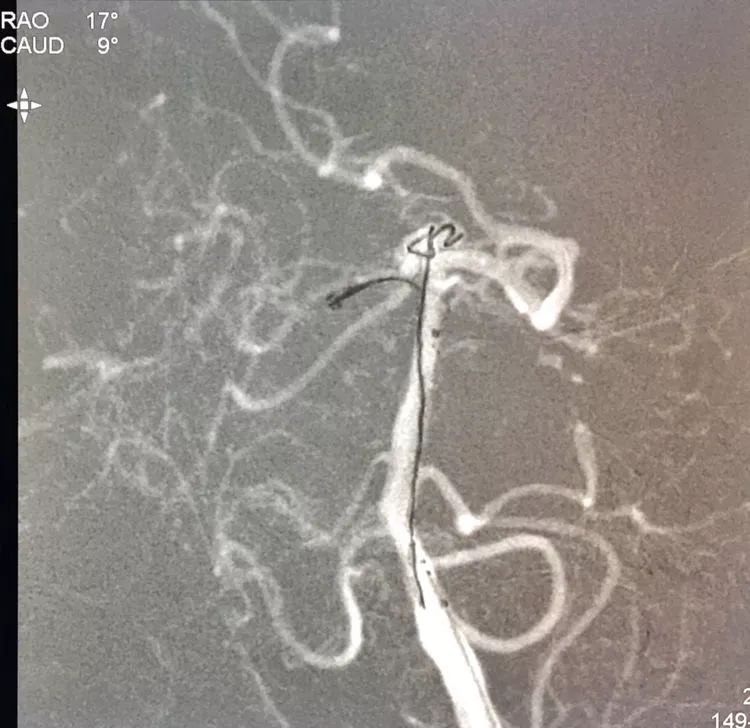

在支架保护下输送弹簧圈栓塞瘤腔

此时从工作位(右斜17°反汤9°)看弹簧圈分布致密,微导管头已被顶到瘤颈处

工作位造影看动脉瘤栓塞满意,子瘤已不显影,是不是可以收手了呢?

旋转增强器透视观察各个投照角度弹簧圈的分布情况,侧位透视发现瘤腔后部的弹簧圈分布疏松,形成死腔,看来革命还未成功,同志尚需努力呀!